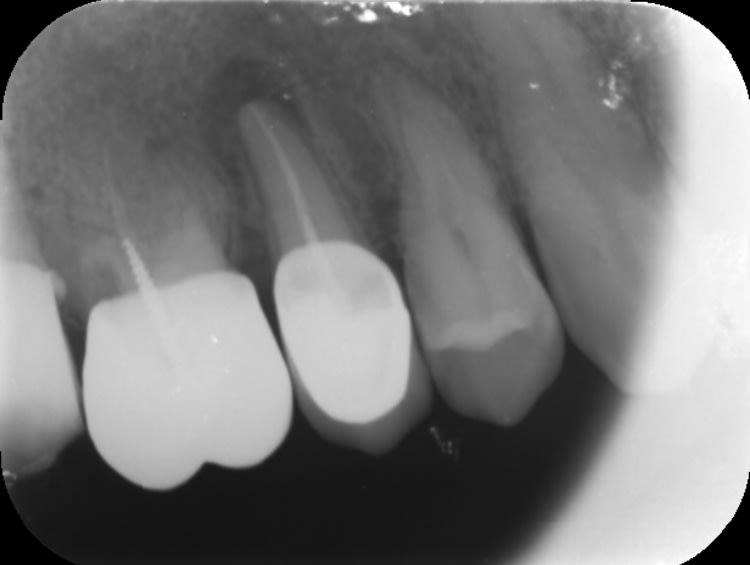

Effectivement première fois que cela m'arrive en 35 ans d'exercice !!

Traitement canalaire de la 47: la pâte à canaux ( Sealite Ultra ) a fusé au dela de l'apex lors de l'obturation à la guttachaude. Malheureusement le canal dentaire passe juste au niveau de l'apex et la pâte est rentré à l'intérieur.

La patiente n'a eu aucun signe pendant 3 jours puis paresthésie au niveau mentonnier ( pas au niveau labial) . La patiente décrit cela comme une fin d'anesthésie.

Quelles sont vos avis sur la récupération de la sensibilité ?

Depuis 3 semaines la paresthésie n'a pas changé ( diminué ou augmenté) .

Désolé pour les images cone beam: je n'arrive pas à les mettre dans le bon sens!!